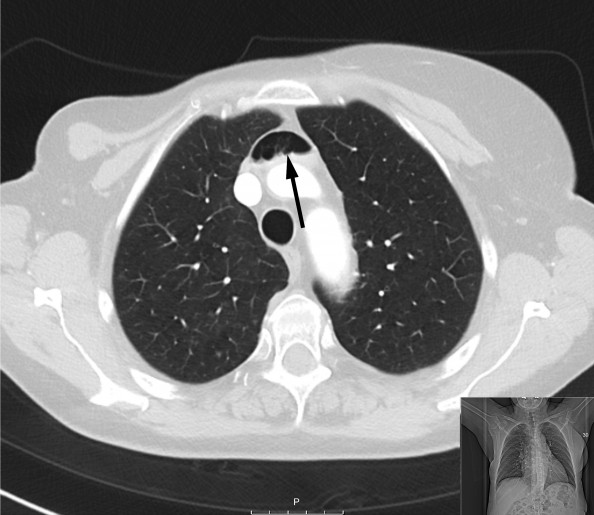

Bildene viser betydelige luftmengder i venesystemet hos en kvinne i 70-årene. Spesielt sees luft i venstre vena brachiocephalica, høyre forkammer og høyre ventrikkel. Grunnet mistanke om sternumfraktur var det rekvirert CT thorax med kontrast. En liten sternumfraktur ble funnet i tillegg til luftemboliene.

Sannsynligvis har det i forbindelse med kontrastundersøkelsen blitt injisert luft venøst. Vakthavende intensivlege ble varslet etter at radiolog hadde gransket bildene, og pasienten ble tilsett umiddelbart. Hun var respiratorisk og sirkulatorisk stabil, med lettgradig dyspné som eneste symptom. Hun ble leiret i venstre sideleie med hodet litt lavere enn kroppen (Durants manøver) og fikk ti liter oksygen på maske med reservoar. Dykkerlege ved Haukeland universitetssykehus ble kontaktet.

Pasienten ble liggende i venstre sideleie i åtte timer med samtidig oksygenbehandling. Deretter ble ny CT thorax gjennomført, og denne viste fullstendig resorpsjon av luftmassene. Pasienten ble så overført til sengepost for lindring av smerter fra sternumfrakturen.